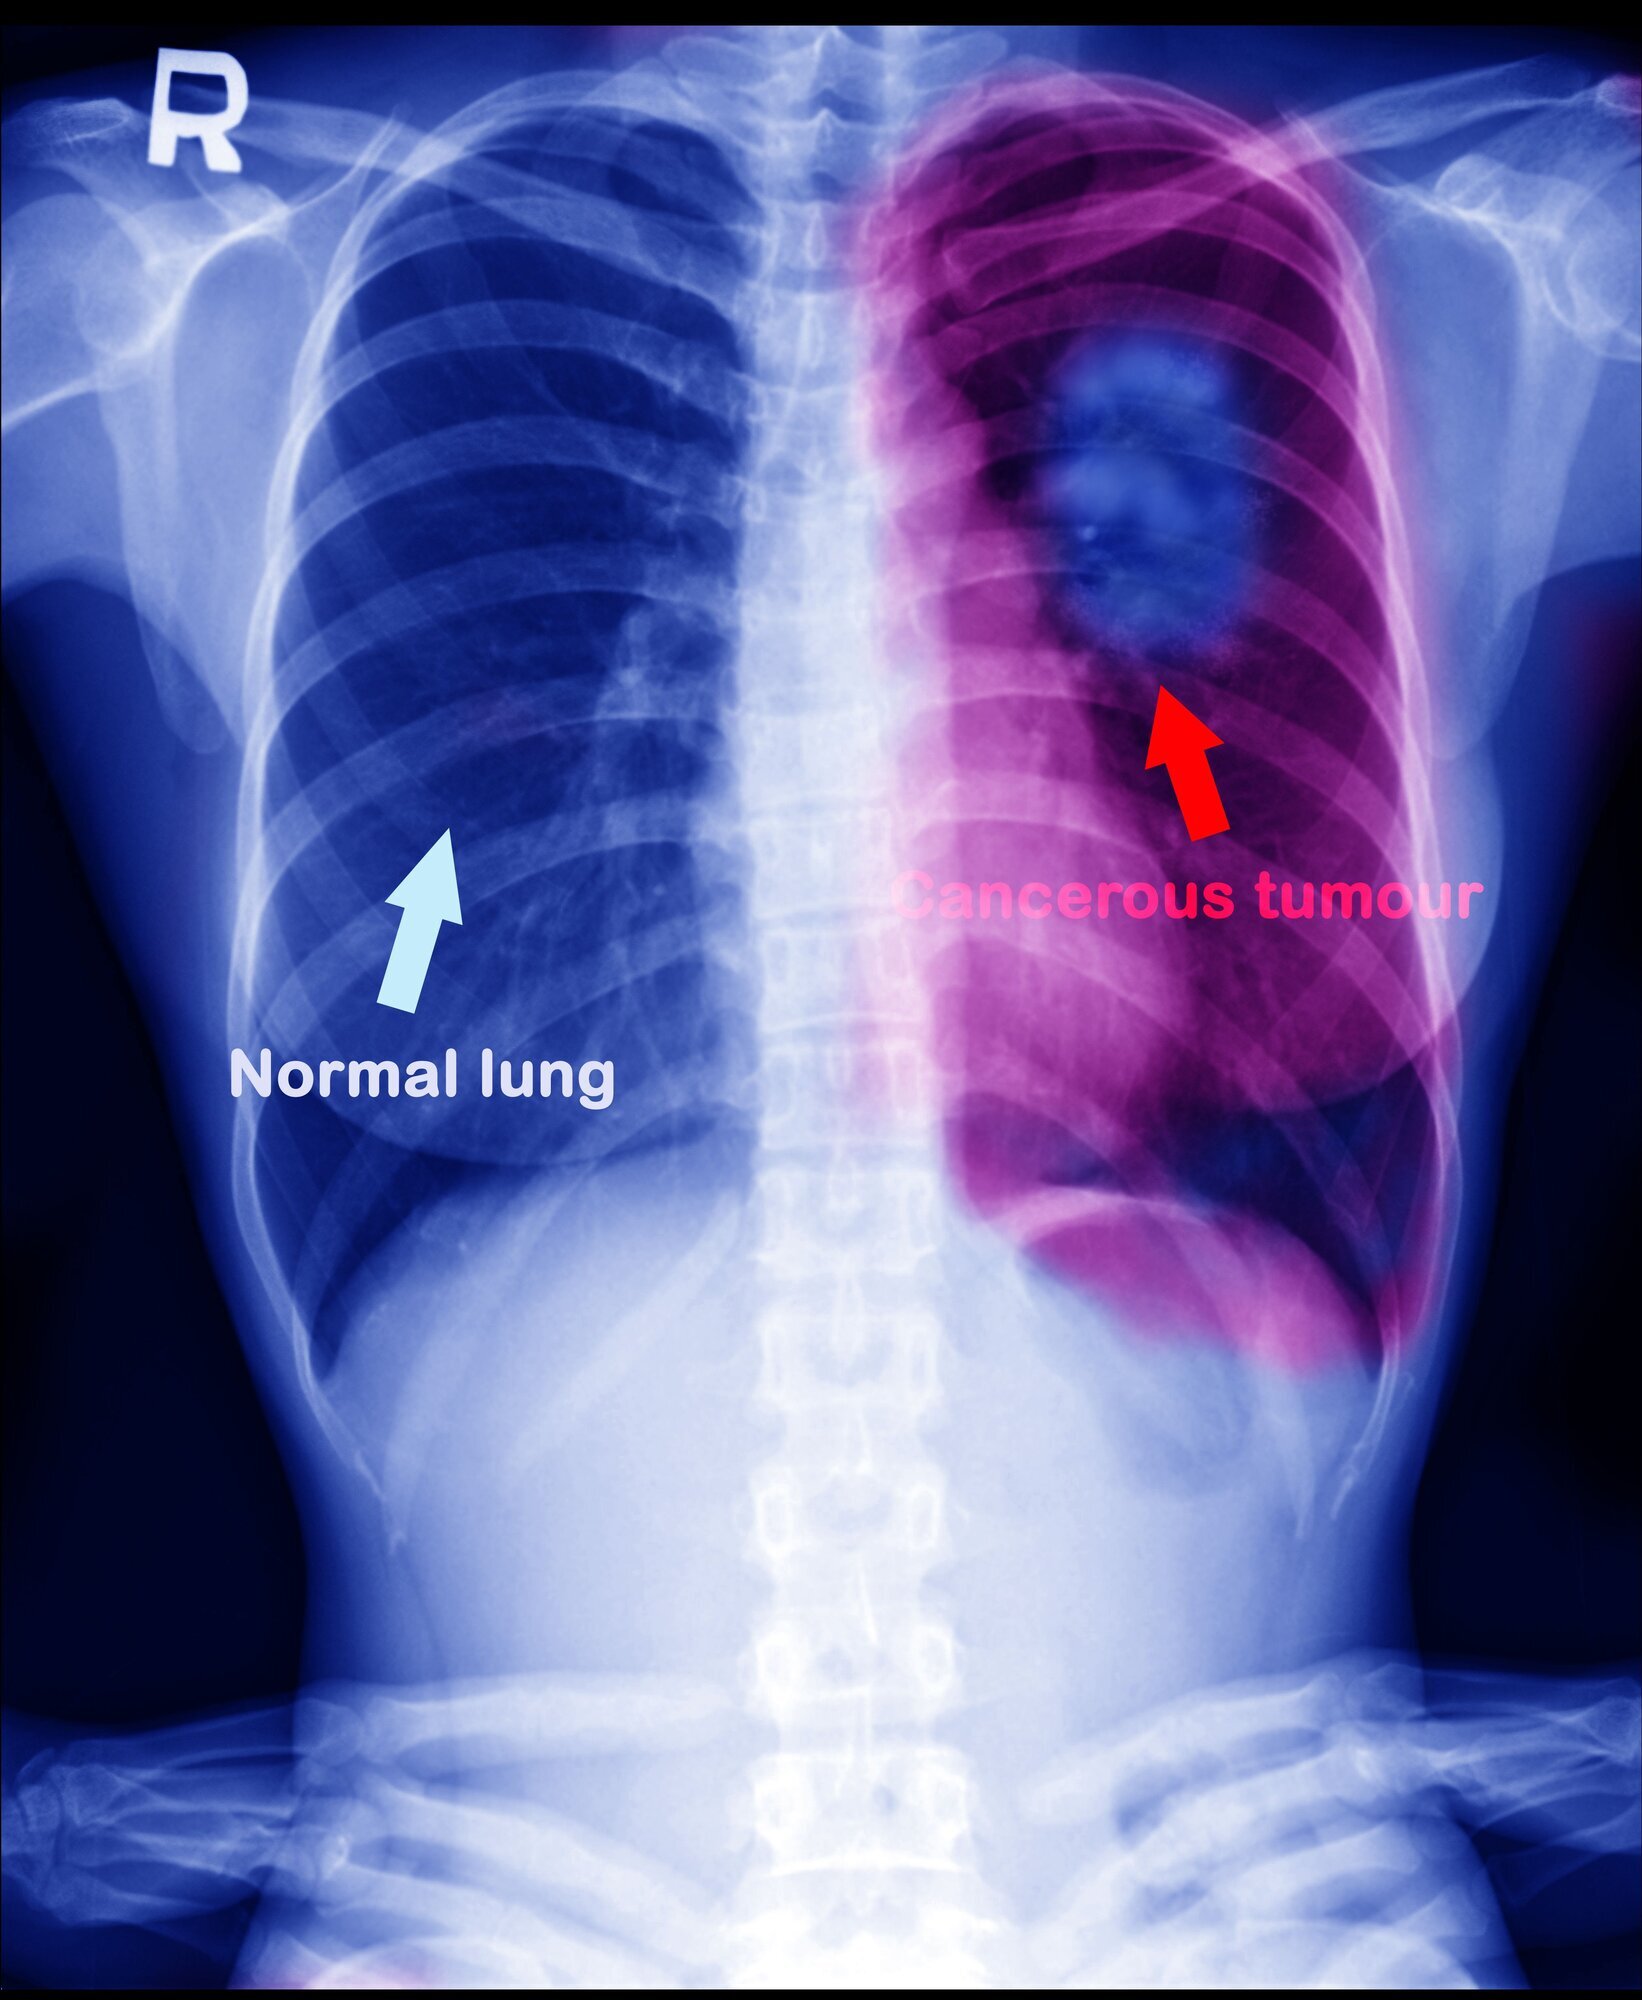

Lungekreft og føflekkreft er to kreftformer som immunterapi har svært god effekt på.